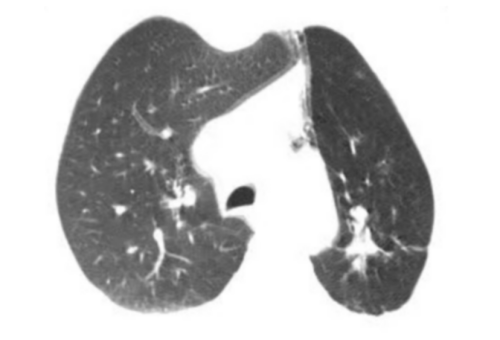

呼吸内镜诊疗部副主任医生刘超群带领团队进一步完善相关术前检查,通过支气管镜和气道内超声,使用高频电刀分次向下,切开长约2cm瘢痕组织,让大量脓液溢出,再通过球囊扩张,扩大其气管,让左主管腔再通,患者咳嗽出大量脓痰,自感气促明显缓解,复查胸部CT,神奇地发现消失的左肺回来了。

复查胸部CT显示左肺复张